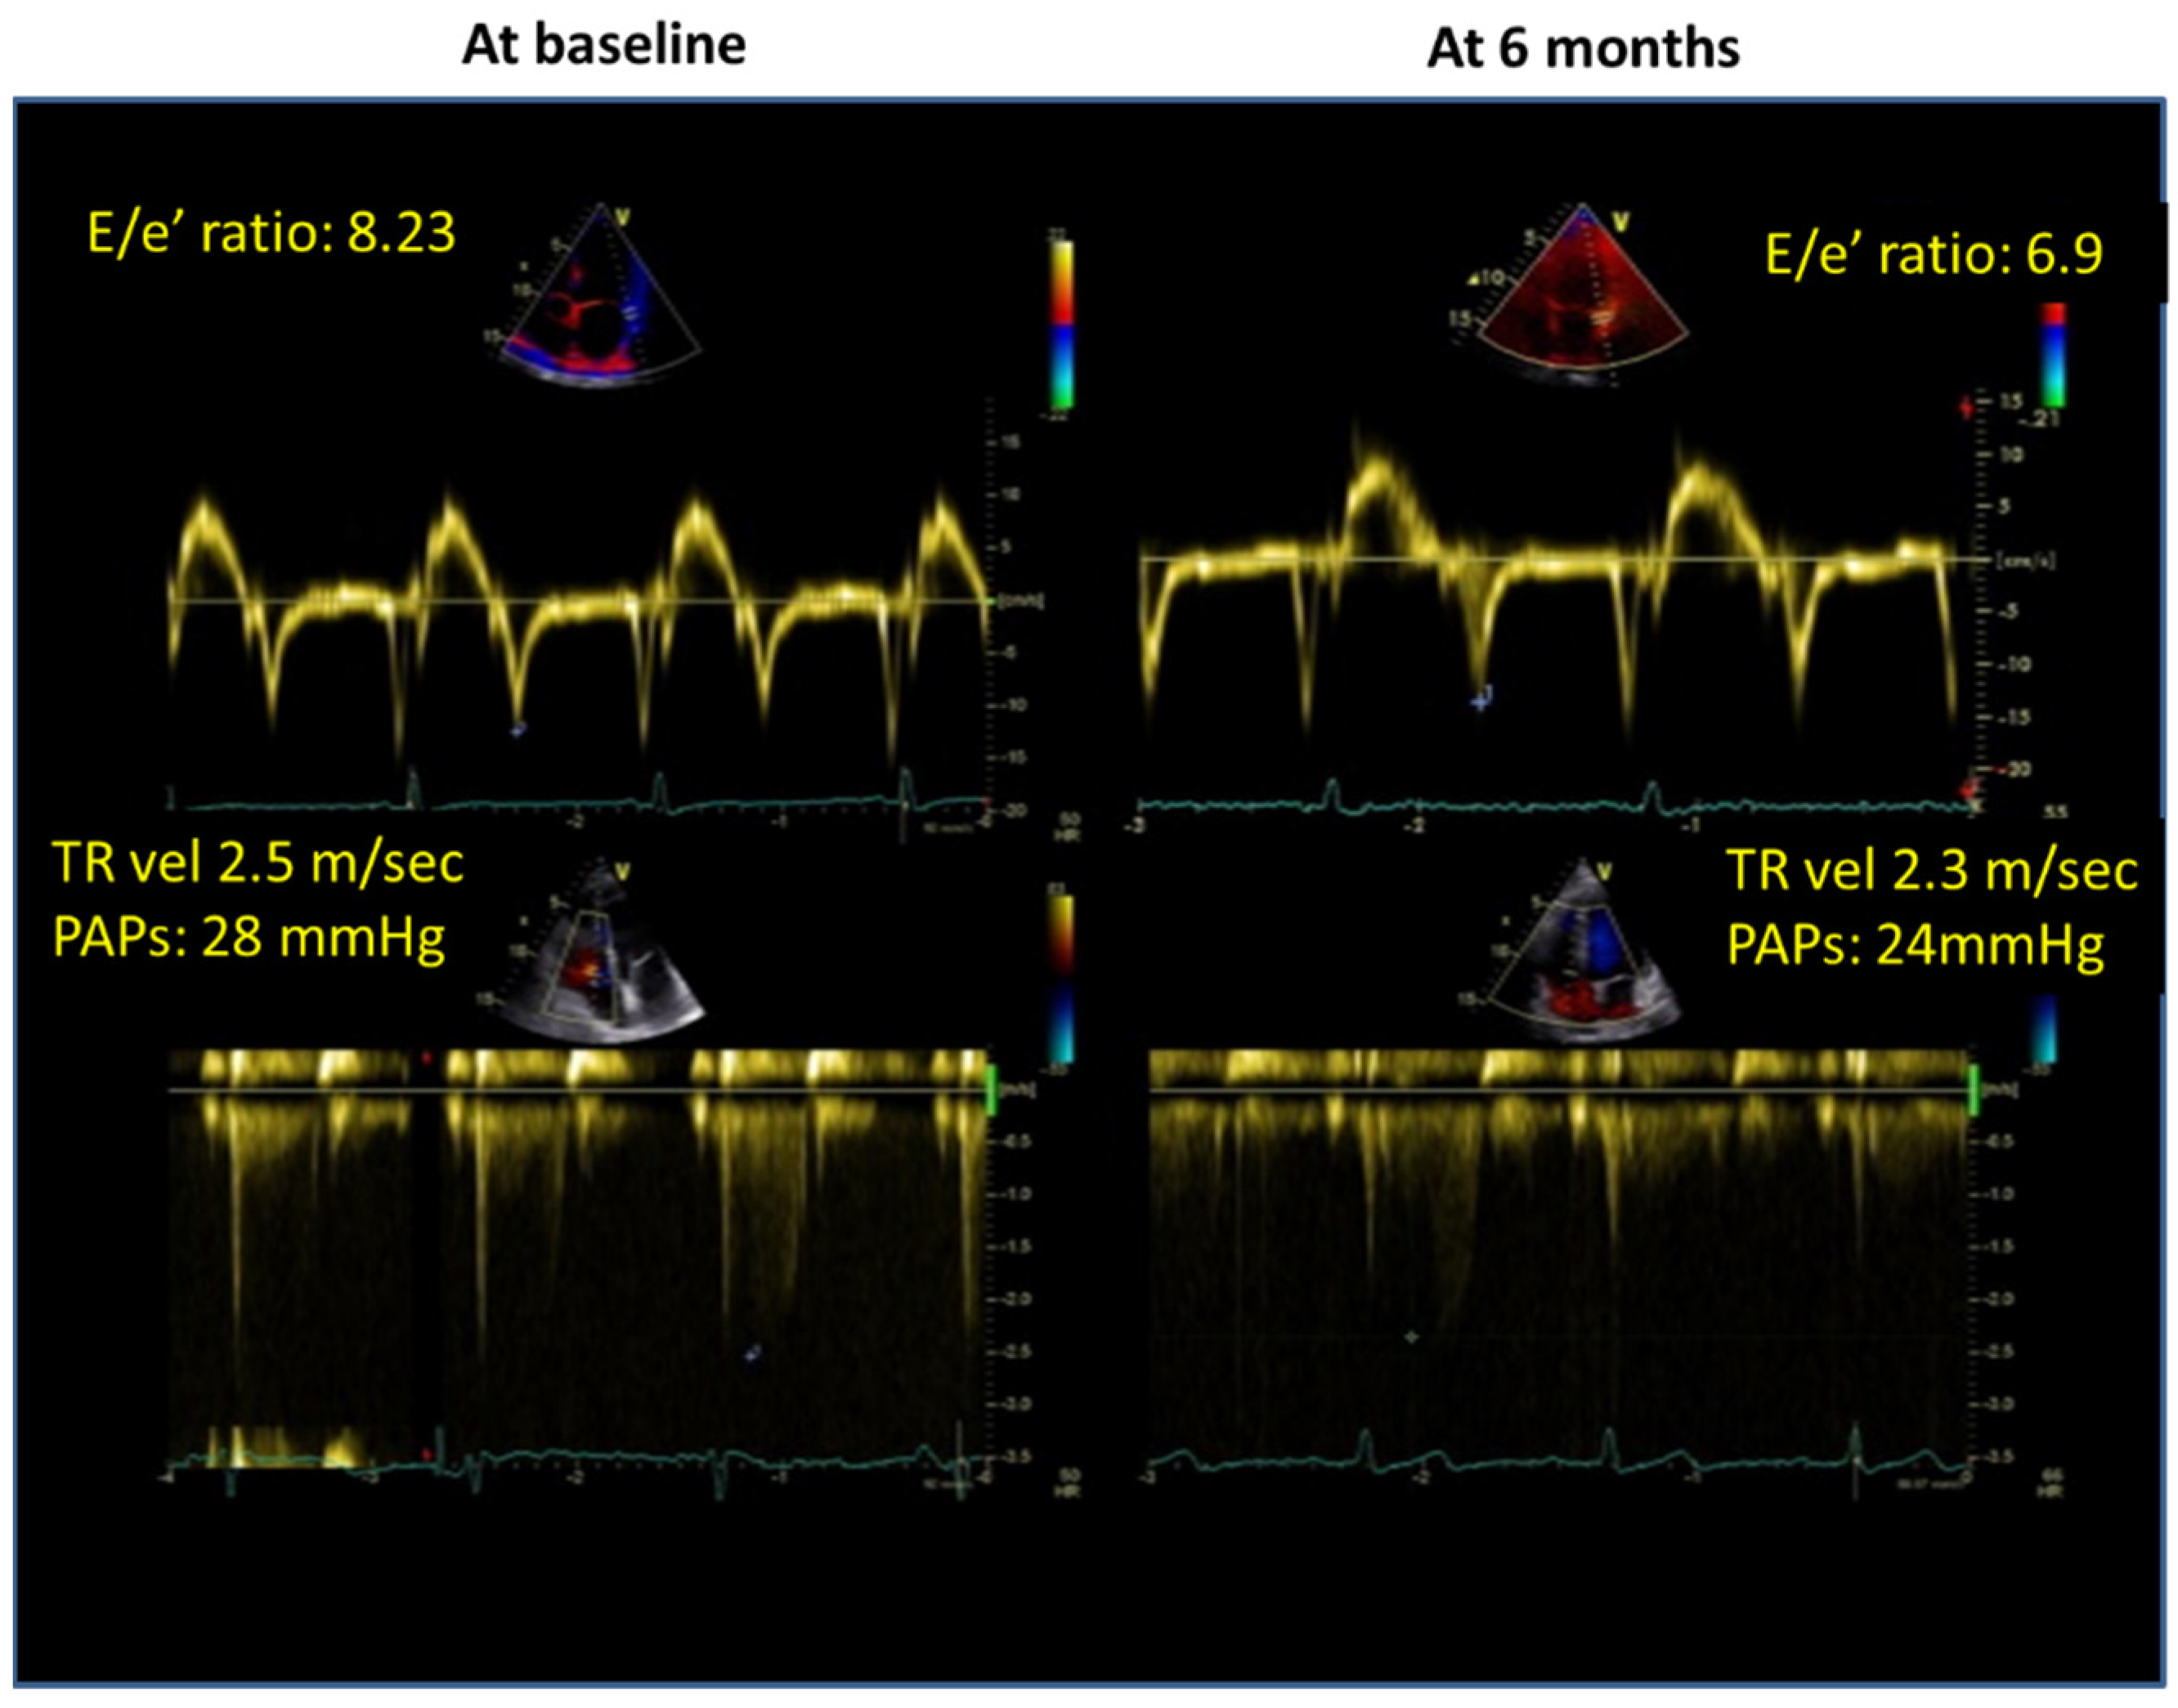

| E/e’ratio | 7.4 ± 2.7 | 6.3 ± 1.3 | 0.03 |

| TR vel (m/s) | 2.4 ± 0.2 | 2.1 ± 0.2 | 0.001 |

| PAPs (mmHg) | 27.3 ± 3.6 | 22.9 ± 5.7 | 0.005 |